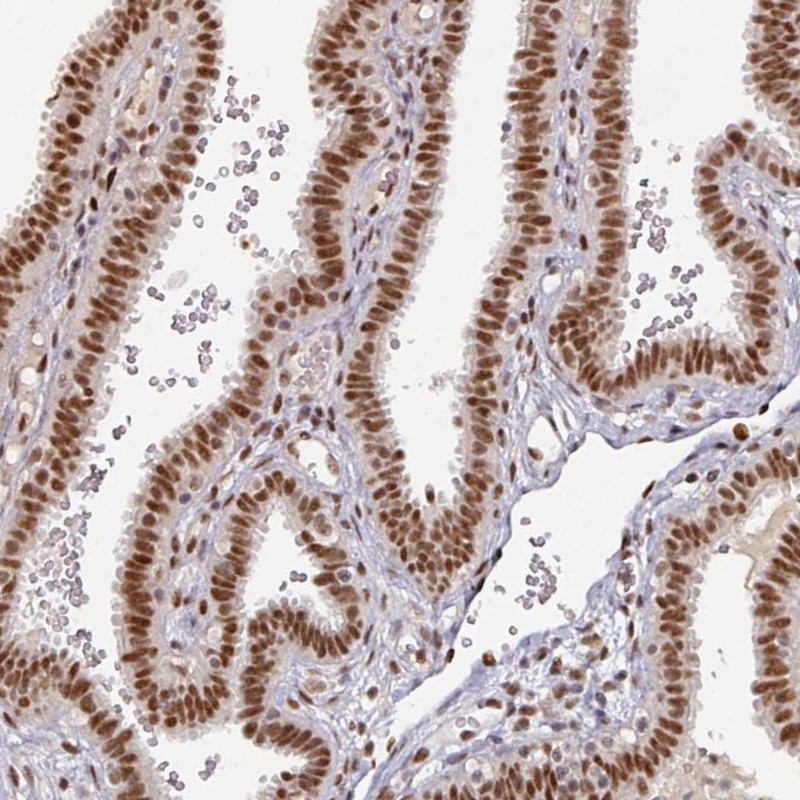

Immunohistochemical staining of human fallopian tube shows strong nuclear positivity in glandular cells.